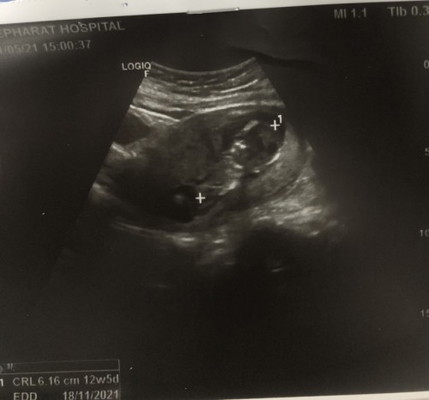

13 wks. มีเลือดออก

แม่ๆท่านใดที่มีประสบการณ์แท้งคุกคามบ้างคะ ท้องสองค่ะท้องแรกแท้งไป พอมาท้องนี้เลยวิตกกังวล ตอนนี้ อายุครรถ์ 13 สัปดาห์ค่ะ มีเลือดออกตั้งแต่ 8 สัปดาห์ มีมาเรื่อยๆ อาทิตย์ละวัน 2 วัน แต่ไม่ใช่เลือดสดเป็นเลือดชมพูจางๆ หาหมอ หมอบอกน้องยังปกติหัวใจเต้นอยู่ แต่แม่ก็ยังกังวลค่ะ กลัวน้องจะไม่อยู่ ล่าสุดฉีดยากันแท้งไปนอนตลอด งานก็ไม่ได้หนักอะไร พอมา 5 วันเลือดก็ยังออกอีก ไปหาหมอ หมอก็ให้สังเกตุอาการค่ะ แม่ๆท่านไหนมีประสบการณ์แบบนี้แชร์หน่อยค่ะ ควรทำอย่างไรดี